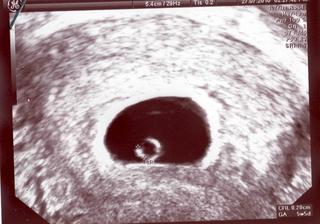

Inak babulky ja som bola dnes v nemocnici, bo som zacala troska spinit, tak som radsej sadla do auta a frcala. Nastaste vsetko ok a dufam, ze to aj tak ostane. Dostala som stiplavu injekciu do zadku a odisla som spokojna 😀 😀 😀 A dostala som fotku 😉

@lenocka80 jeeeeeeeeeeeeeeeeej Malá piškótka Hlavne sa opatruj 😉

@lenocka80 pekna fotecka ... davaj na seba pozor 😉